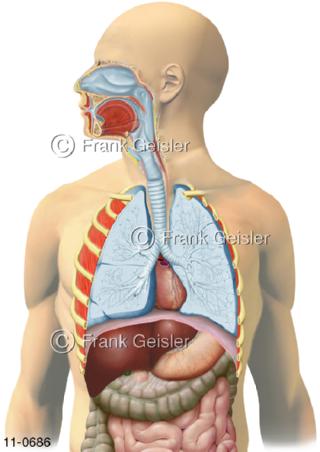

11-0686 Übersicht Atemtrakt, Luftwege Atemwege